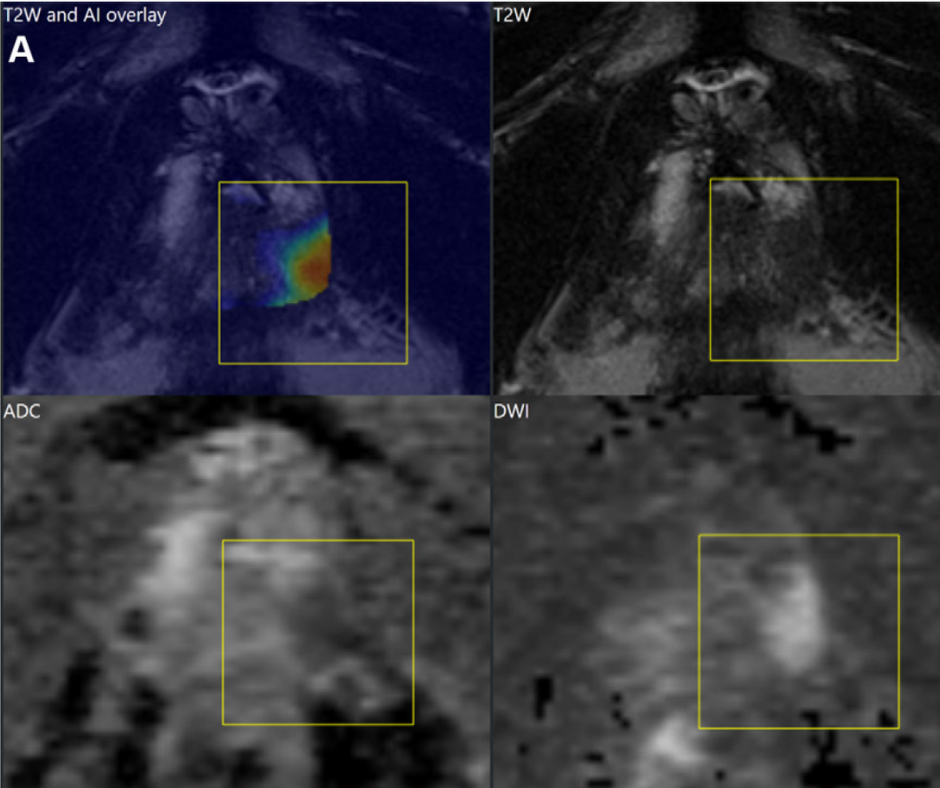

The use of an adjunctive deep learning (DL) software made no difference in the diagnosis of clinically significant prostate cancer (csPCa) with bi-parametric magnetic resonance imaging (MRI), according to newly published research. The study authors also noted the DL software showed no difference in the consistency of scoring with the Prostate Imaging-Reporting and Data System (PI-RADS) for radiologists of varying experience levels.

In assessing the area under the receiver operating curve (AUROC) for the detection of csPA, the study authors said the DL software showed no difference in the AUROC for any of the radiologists. They also noted significantly higher AUROCs for the radiologist with more than 20 years of experience (92 percent) and a radiologist with five years of experience (85 percent) in comparison to standalone use of the DL software (74 percent).

“Overall, the radiologists changed their initial PI-RADS scores in ~ 1% of the scans with the DL software, and radiologists with > 5 years of experience provided a statistically higher performance in identifying csPCa than the DL software. Furthermore, the DL software did not improve radiologists’ performance in identifying csPCa,” wrote study co-author Ercan Karaarslan, M.D., a professor of radiology at the School of Medicine at Acibadem Mehmet Ali Aydinlar University and director of radiology at the Acibadem Maslak Hospital in Istanbul, Turkey, and colleagues.